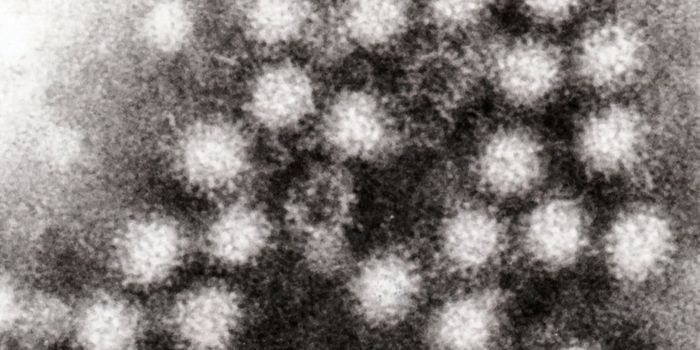

AUG 05, 2015Health & MedicineHuman norovirus is a member of the Caliciviridae family of viruses which are single-stranded RNA nonenveloped viruses th ...